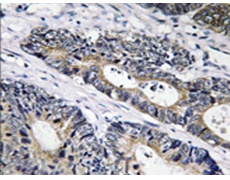

IHC |

IHC positive control: |

Human colon carcinoma tissue |

IHC Recommend dilution: |

50-100 |